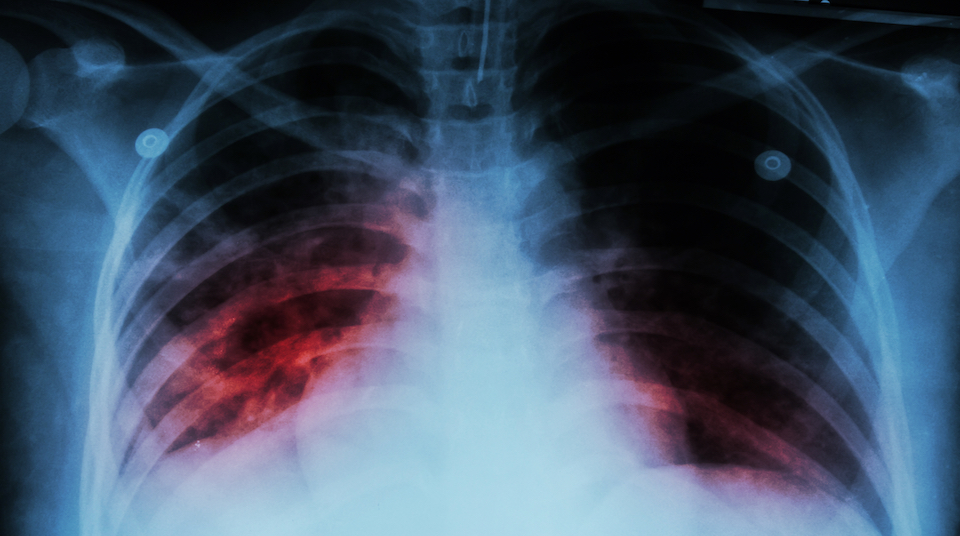

World Pneumonia day

It is the single largest infectious killer of children worldwide. Yet despite having been recognised as an endemic disease since Ancient Greek times – pneumonia continues to take the lives of more than 100 children every hour, every day.